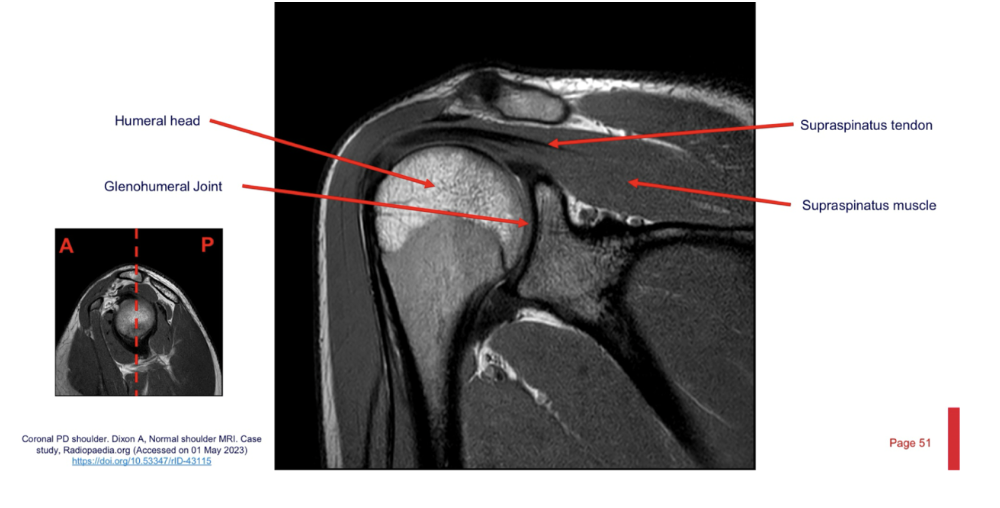

Sequence + pathology?

• PD, PDFS

• Path = supraspinatus tendon tear

• -  You can follow the tendon and see that it stops just above the humeral head rather than

attaching to the lateral aspect of the head.

• -  More prominent of the PDFS you can see high signal around the lateral aspect of the humerus

indicative of a pathological process occurring because of the tear.

What is the most common rotator cuff tendon tear?

• Supraspinatus tendon